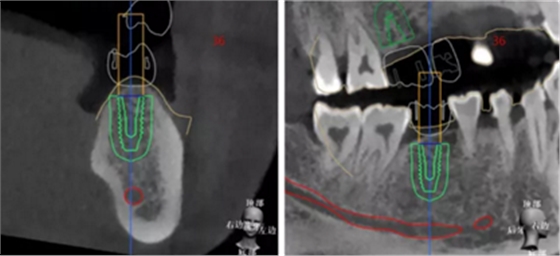

查看種植體螺絲通道穿出虛擬修復(fù)體的位置。

查看種植體在牙槽嵴頂穿出位置。

種植規(guī)劃與術(shù)后CBCT影像對比